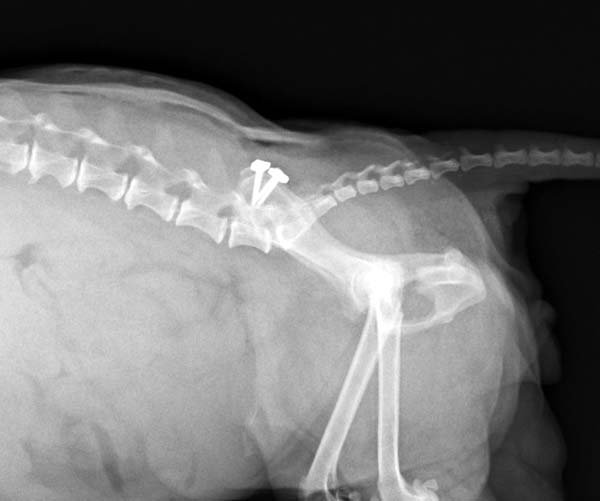

13歳のマルチーズちゃんが骨盤骨折で来院されました。ロッキングプレートを使用した仙腸関節安定化術(TAITAN1.7と1.5)で固定する手術を行いました。術後元気に歩けるようになりました。よかったね。